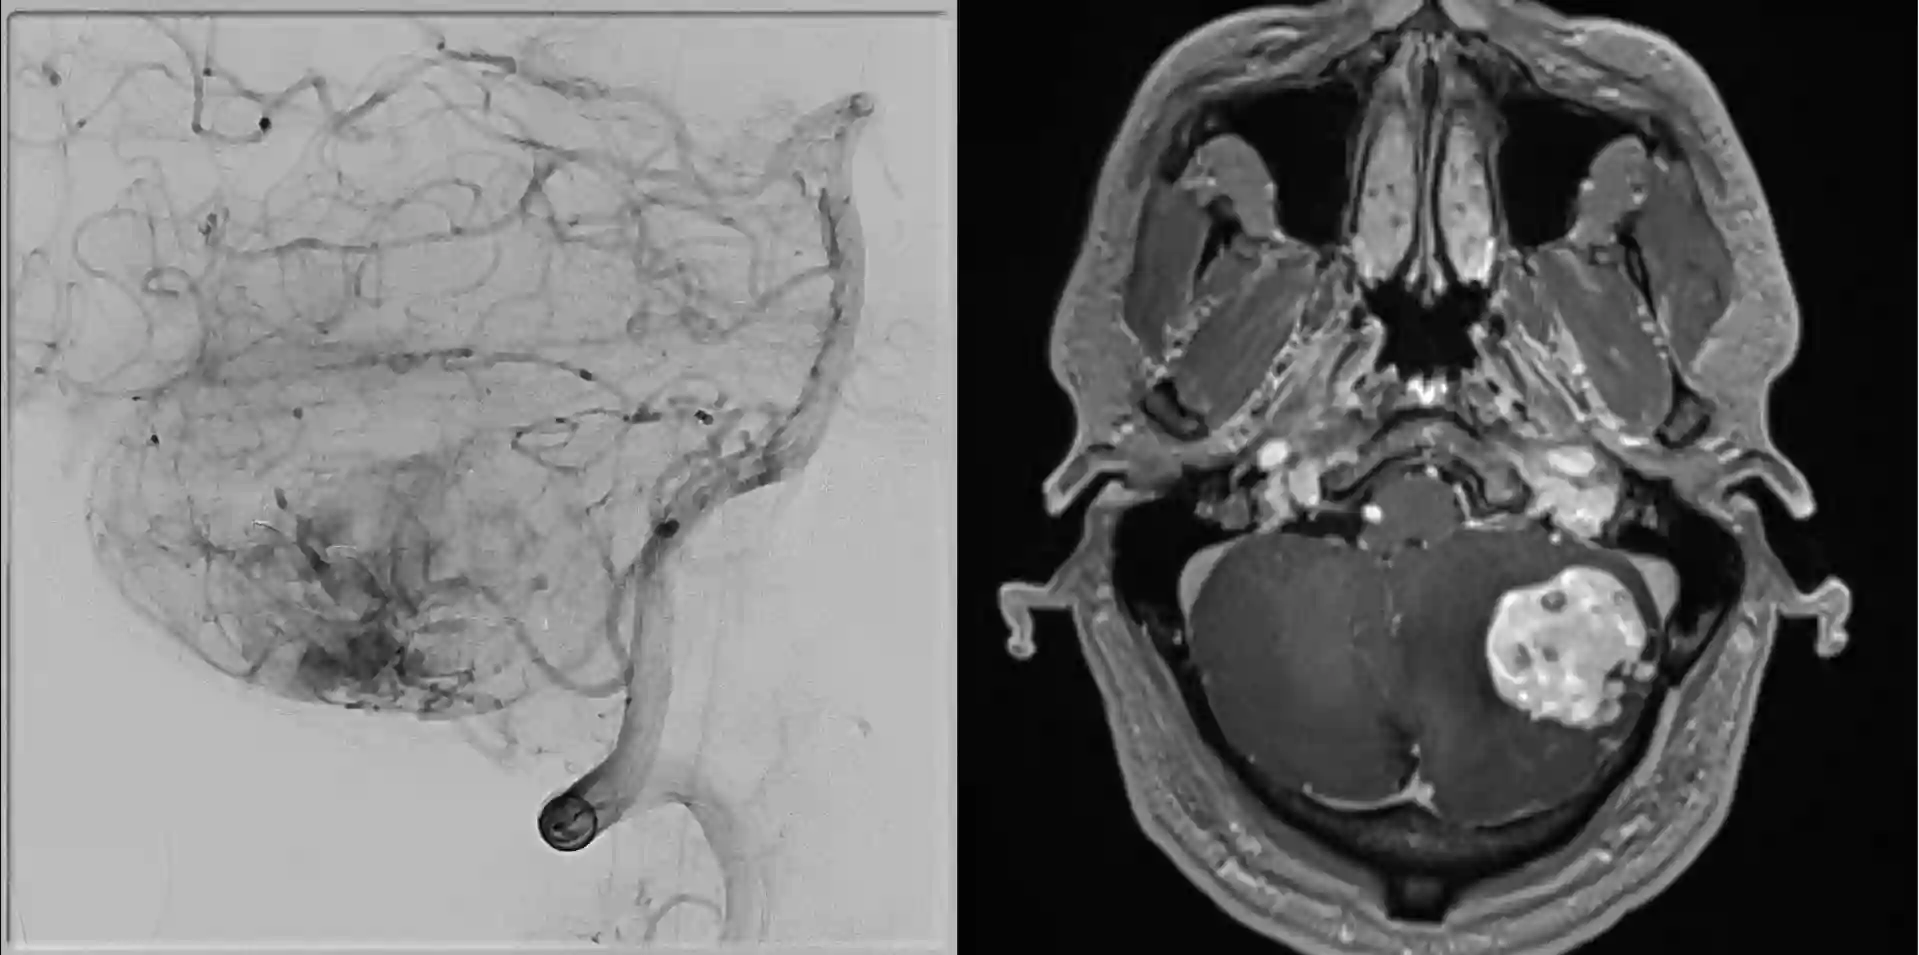

Bildgebung

Der Goldstandard in der Bildgebung von Hämangioblastomen ist die MRT Bildgebung. In einer digitalen Subtraktionsangiographie zeigt sich häufig ein stark vaskularisierter Nodulus mit Feedergefäßen, welcher suggestiv für ein Hämangioblastom ist.